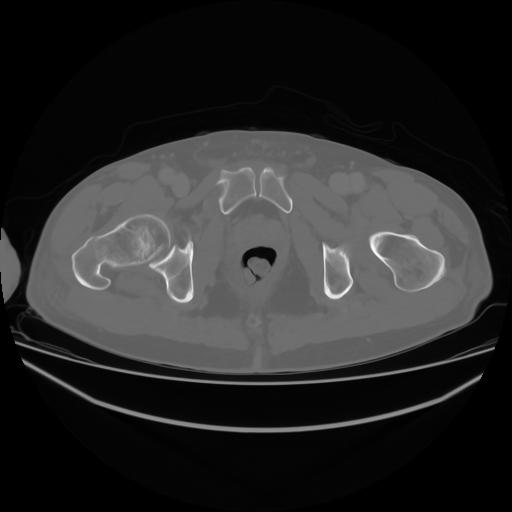

4 CUERPO,CE,Axial,3.0,CUERPO,,